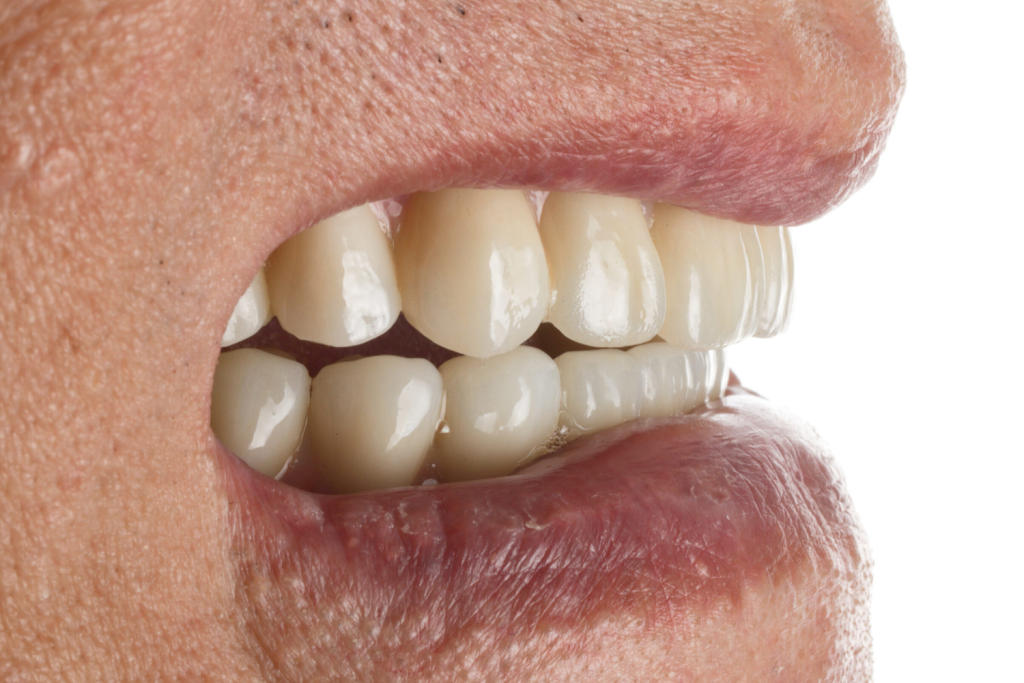

術後正式假牙

術後配戴正式假牙